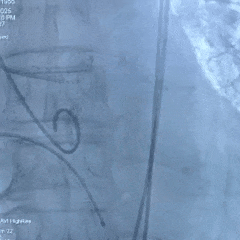

手术过程

左侧冠脉造影

右侧冠脉造影并行PCI

根部造影

可见瓣叶钙化,伴反流

TF21瓣膜0位初始释放

全展开后多角度根部造影:瓣膜深度形态合适,冠脉灌注良好,少量瓣周漏,选择解锁脱钩

脱钩后造影评估:瓣膜深度可,展开良好,少量瓣周漏

外周造影检查,血管无损伤